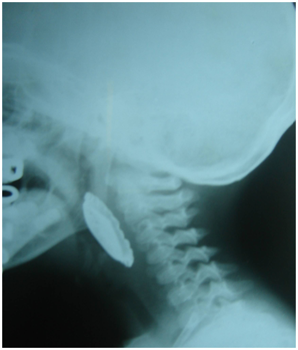

A 14 year old boy presented with difficulty and pain in swallowing for 6 hours. The symptoms started whilst he was playing with a soda cap in his mouth, which he accidently ingested. On examination there was mild tenderness on the neck and minimal drooling of saliva. The x-ray of the neck lateral (Figure 1) and antero-posterior view revealed a radio opaque foreign body in the neck, the level of which ranged from cervical vertebrae 3 to 6. The patient was taken to the emergency operation theatre and the soda cap (Figure 2) was removed using a rigid esophagoscope. There was minimal mucosal injury and the patient was started on oral feeds the next day. He has been asymptomatic at 2 months follow up.

Figure 1 Xray lateral view of the neck showing the soda cap foreign body.